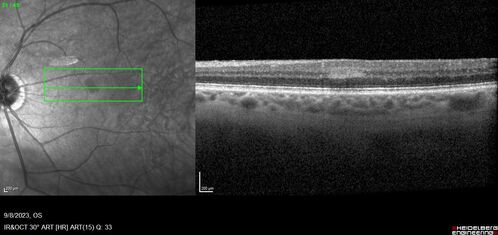

Paracentral acute middle maculopathy - isolated

83 year old man New spot in the vision yesterday left eye.

Medical Hx: Pure Hypercholesterolemia

Systemic Meds: Crestor.

VA OD: Dcc20/20

VA OS: Dcc20/20

IOP: TP: OD:19 OS:10

Isolated PAMM lesion